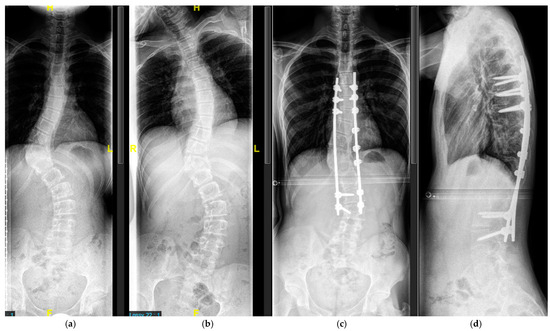

4.2.2. Adolescent Spinal Deformity

5.2.2. Definitive Spinal Fusion